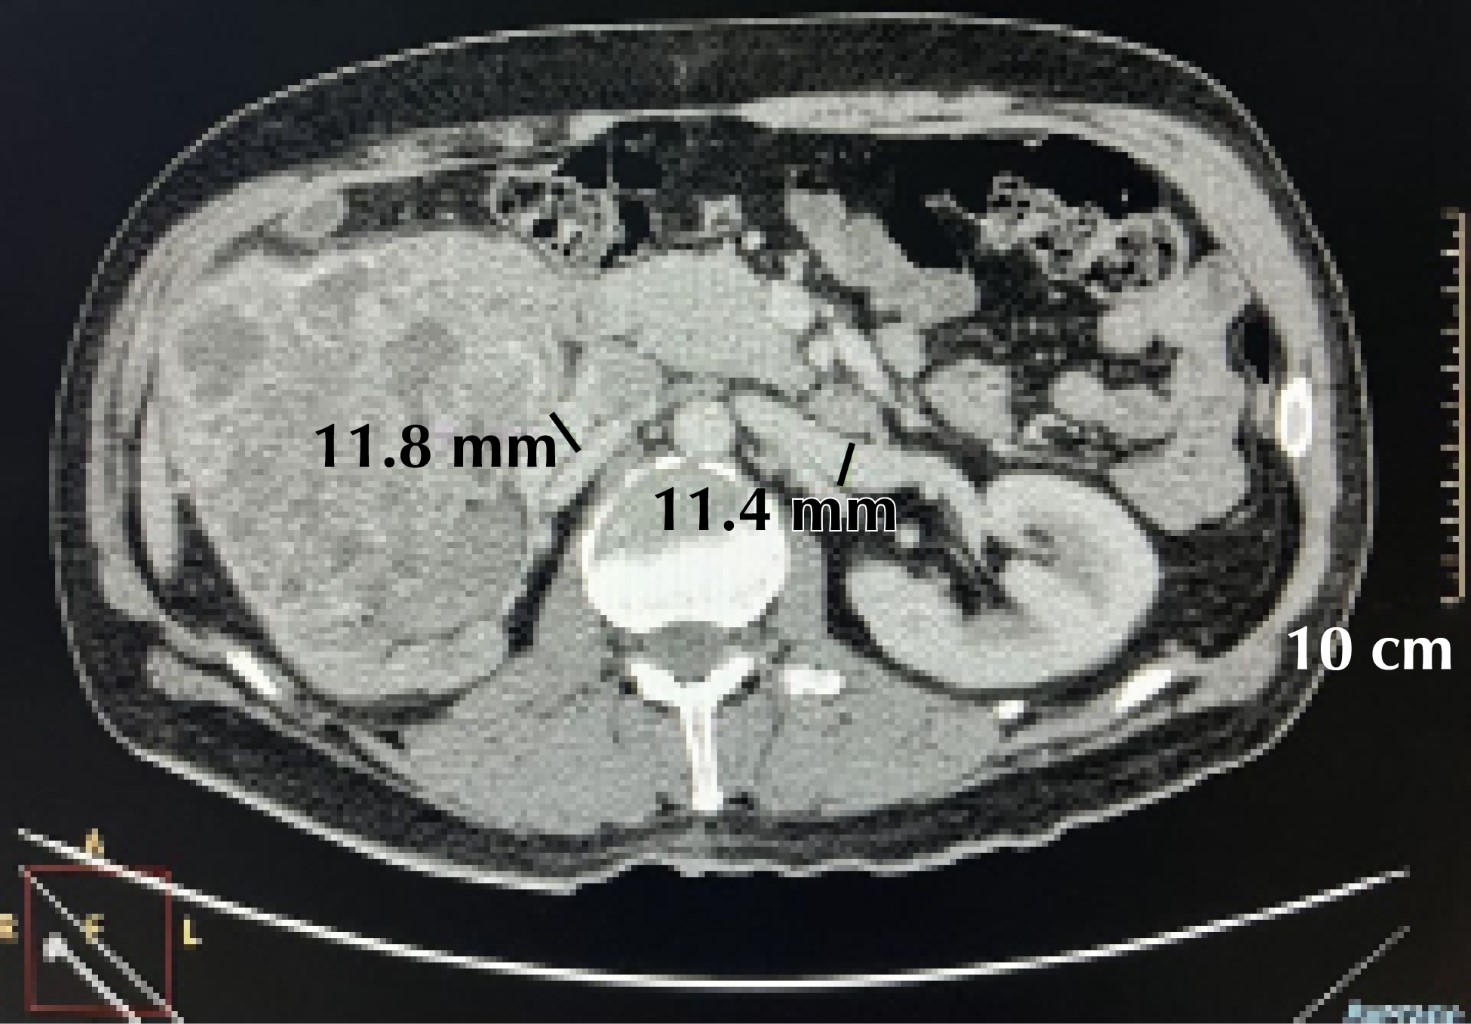

Figure 2